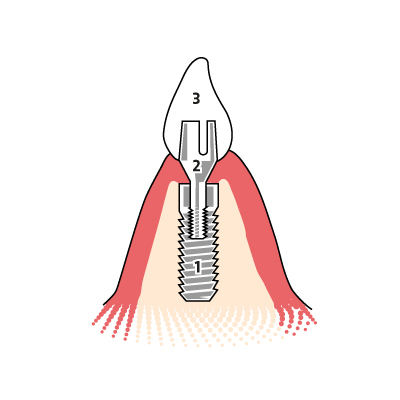

Aufbau eines zweiteiligen Zahnimplantats mit künstlicher Krone

1: Implantatkörper

Der Implantat-Körper wird fest im Kieferknochen (hier im Bild sandfarben dargestellt) verankert und muss dort einheilen, um die Funktion einer Zahnwurzel zu übernehmen. Damit das Implantat fest verankert werden kann, muss der Kieferknochen ausreichend dick sein. Andernfalls muss vor dem Setzen ein Knochenaufbau erfolgen.

2: Abutment

Der Implantat-Aufbau (Abutment) mit Halteschraube dient als Verbindungsteil zwischen Krone und Implantat-Körper. Das Abutment ist nicht sichtbar, sondern im Implantat, Zahnfleisch und in der Krone verborgen. Das Abutment eines Implantats besteht in der Regel aus Titan. Es gibt aber auch Ausführungen in Keramik.

3: Suprakonstruktion

Die Implantat-Krone (Suprakonstruktion) ist der eigentliche Zahnersatz und wird am Abutment befestigt. Statt einer einfachen Krone können auch aufwendige Konstruktionen auf Implantaten befestigt werden.